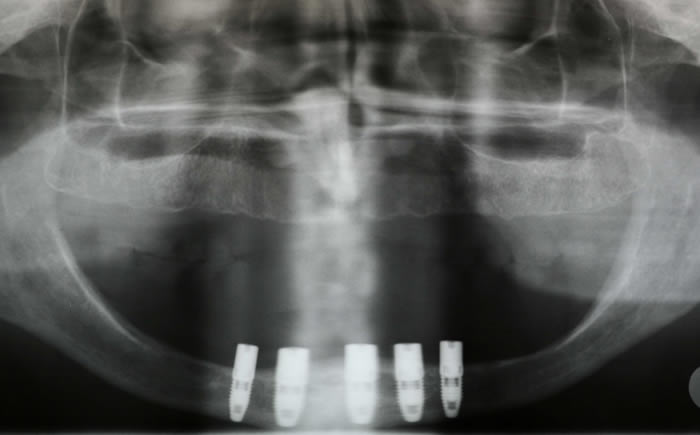

Full arches of teeth replaced by dental implants

Case One (5 images)

Full set of lower teeth fixed onto five dental implants.

Case Two (8 images)